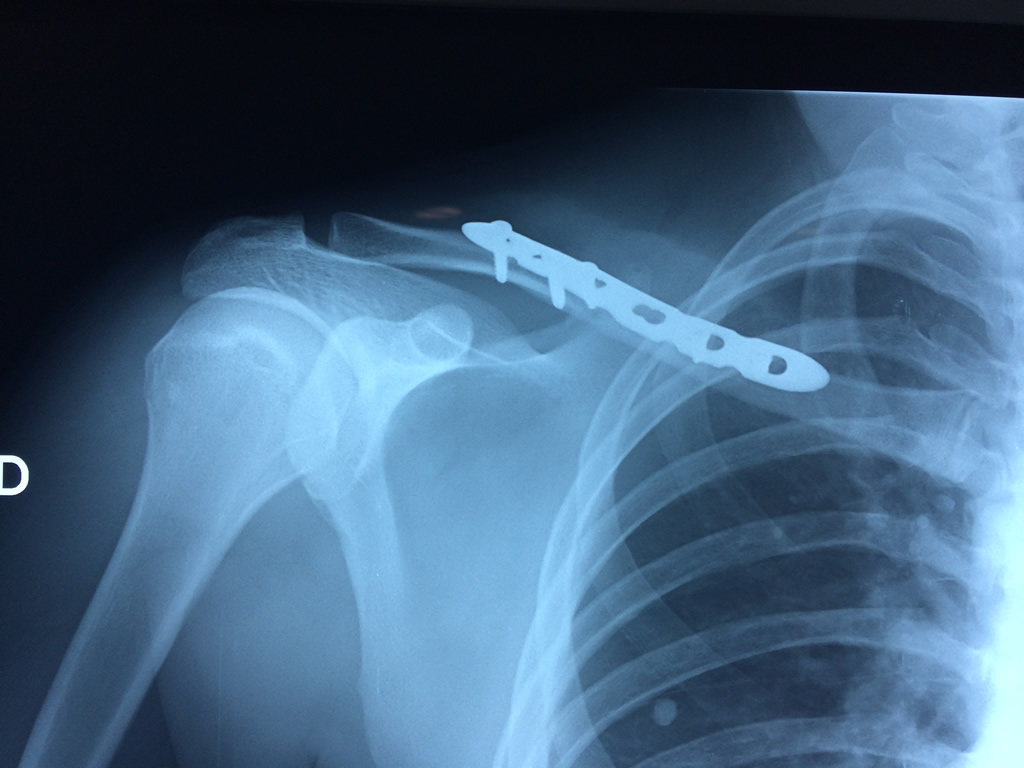

Cirugías de Hombros - Clavícula

La clavícula es un hueso largo, con forma de "S" itálica, situado en la parte anterosuperior del tórax. Junto con la escápula forman la cintura escapular. Se puede palpar por toda su longitud y se extiende del esternón al acromion de la escápula, siguiendo una dirección oblicua lateral y posterior.

Se considera el único medio de unión entre el miembro superior y el tórax. A pesar de su aspecto, similar al de un hueso largo, posee una estructura semejante a la de un hueso plano, ya que carece de epífisis y de diáfisis, lo que la harían entrar dentro de la clasificación de hueso largo. Carece de un canal medular propiamente dicho.